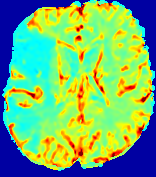

LesionRefer to captionRefer to captionRefer to captionRefer to captionRefer to captionRefer to caption𝐕rgbsubscript𝐕𝑟𝑔𝑏{\bf{V}}_{rgb}Refer to captionRefer to captionRefer to captionRefer to captionRefer to captionRefer to caption𝐕2subscriptnorm𝐕2{\|\bf{V}}\|_{2}Refer to captionRefer to captionRefer to captionRefer to captionRefer to captionRefer to captionRefer to caption3.53.53.52.82.82.82.12.12.11.41.41.40.70.70.70.00.00.0(mm/s)𝑚𝑚𝑠(mm/s)D𝐷DRefer to captionRefer to captionRefer to captionRefer to captionRefer to captionRefer to captionRefer to caption0.0200.0200.0200.0160.0160.0160.0120.0120.0120.0080.0080.0080.0040.0040.0040.0000.0000.000(mm2/s)𝑚superscript𝑚2𝑠(mm^{2}/s)Slice #1Slice #2Slice #3Slice #4Slice #5Slice #6

Figure 3: PIANO feature maps for one stroke patient, where the lesion is located in the left hemisphere. Top row: segmented stroke lesion region (white) on different slices, obtained from ISLES 2017. The corresponding slices for the PIANO feature maps are shown in the following rows.

For a better insight into an estimated velocity field 𝐕𝐕{\bf{V}} and diffusion field 𝐃𝐃{\bf{D}}, we compute the following maps: (1) 𝐕rgbsubscript𝐕𝑟𝑔𝑏{\bf{V}}_{rgb}: Color-coded orientation map of 𝐕=(Vx,Vy,Vz)T𝐕superscriptsuperscript𝑉𝑥superscript𝑉𝑦superscript𝑉𝑧𝑇{\bf{V}}=(V^{x},V^{y},V^{z})^{T}, obtained by normalizing 𝐕𝐕{\bf{V}} to unit length and mapping its 3 components to red, green, blue respectively; (2) 𝐕2subscriptnorm𝐕2\|{\bf{V}}\|_{2}: 222 norm of 𝐕𝐕{\bf{V}}; (3) D𝐷D: scalar field in Eq. 5.

Fig. 3 and Fig. 4 show the PIANO feature maps estimated from two ISLES 2017 patients: all are highly consistent with the lesion in both cases. Details of the blood flow trajectories are revealed in 𝐕rgbsubscript𝐕𝑟𝑔𝑏{\bf{V}}_{rgb} by the ridged patterns and the sharp changes of colors in the unaffected (right) hemisphere, while the flat patterns appearing within the lesion provide little directional information about the velocity and indicate low velocity magnitudes. Velocity magnitudes are more directly visualized via 𝐕2subscriptnorm𝐕2\|{\bf{V}}\|_{2}, from which one can easily locate the lesion where 𝐕2subscriptnorm𝐕2\|{\bf{V}}\|_{2} is low. D𝐷D also indicates lower diffusion values in the lesion, though with less contrast potentially due to the fact that it captures the accumulated effect of CA diffusion at the voxel-level.